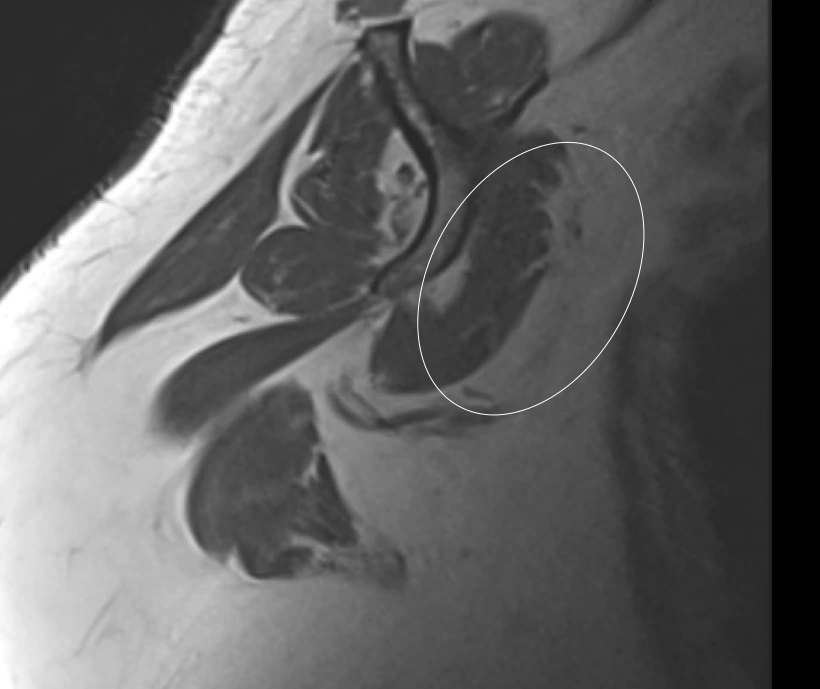

Failure to describe the muscle atrophy accompanying this rotator cuff tear represents a missed chance to flag that the patient may be a poor candidate for surgery and unlikely to recover well.

Atrophied

Normal